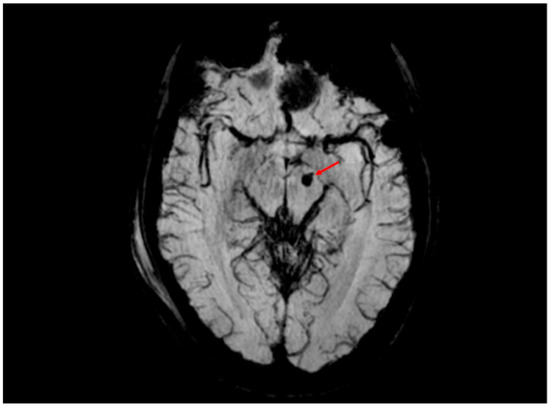

5.3.1. Radiological Findings in Adult DAI

- Abu Hamdeh, S.; Marklund, N.; Lannsjö, M.; Howells, T.; Raininko, R.; Wikström, J.; Enblad, P. Extended anatomical grading in diffuse axonal injury using MRI: Hemorrhagic lesions in the substantia nigra and mesencephalic tegmentum indicate poor long-term outcome. J. Neurotrauma 2017, 34, 341–352. [Google Scholar] [CrossRef]